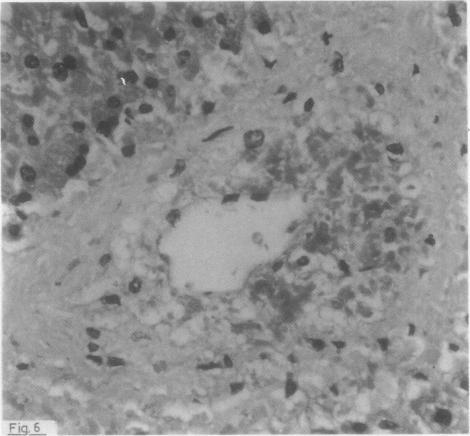

Lesions of hepatic veno-occlusive disease were found in the needle biopsy specimen of one patient suffering from chronic granulocytic leukaemia and in the liver at necropsy of a second patient suffering from acute myeloid leukaemia. The treatment included administration of 6-thioguanine which was the only relevant compound used in the first patient and which was combined with cytosine arabinoside in the second patient.

在一名慢性粒细胞白血病患者的针吸活检标本中以及另一名急性髓细胞白血病患者尸检的肝脏中发现了肝静脉闭塞性疾病病变。治疗包括给予6-硫鸟嘌呤,这是第一名患者使用的唯一相关化合物,在第二名患者中则与阿糖胞苷联合使用。